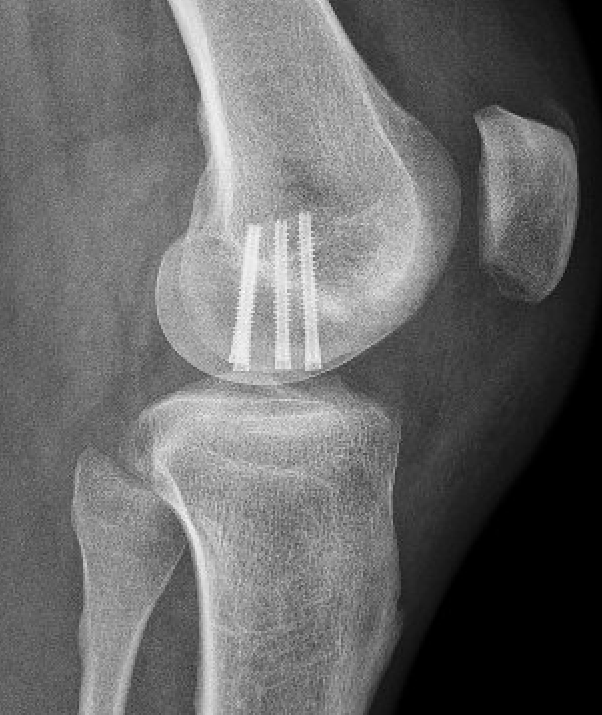

Open reduction and internal fixation

Approach

Patella - medial parapatellar approach with knee extended

Lateral femoral condyle - lateral parapatellar approach with knee flexed to 90

Fixation

Headless compression screws

Large osteochondral fracture medial facet patella